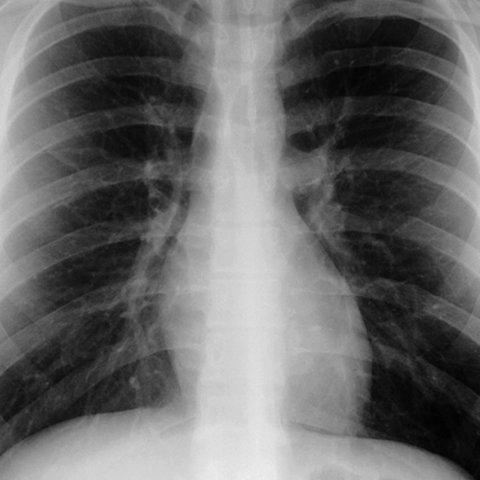

Normal Heart (PA CXR) [1 of 6]